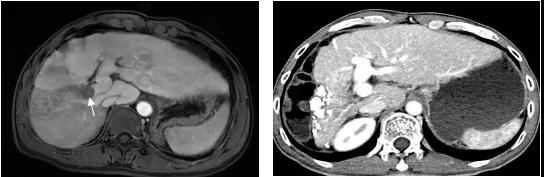

图4、该例肝右叶巨大肝癌合并门静脉右支癌栓(左图,箭头示癌栓),采用TACE治疗肝内肿瘤和放射性粒子治疗门静脉癌栓,术后19个月肝右叶肿瘤几乎完全坏死缩小,而粒子阻止了癌栓进展到主干,门静脉主干保持通畅(右图),现患者已生存5年。